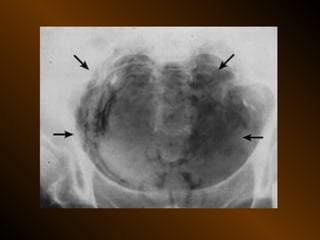

KHÍ TỰ DO

TRONG KHOANG PHÚC MẠC

NGUYÊN NHÂN

thủng tạng rỗng

nguồn gốc xuyên phúc mạc

nguồn gốc trong phúc mạc

10 – 15% thủng tạng rỗng → không thấy hơi tự do ổ bụng

KHÍ TỰ DO TRONGKHOANG PHÚC MẠC NGUYÊN NHÂN thủng tạng rỗng nguồn gốc xuyên phúc mạc nguồn gốc trong phúc mạc 10 – 15% thủng tạng rỗng → không thấy hơi tự do ổ bụng